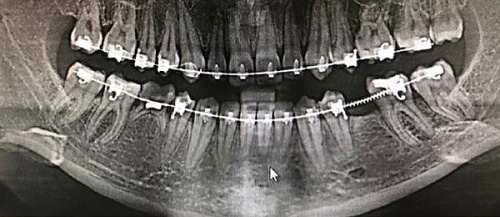

Изменения тканей, которые окружают корни зубов, к сожалению, неизбежны и с возрастом наблюдаются у всех, однако в разном объеме. Так, на развитие пародонтита влияет болезнетворная микрофлора полости рта, которая есть у каждого из нас, но на мы в силах повлиять на ее количество.

Сохранить зубы и пародонт помогает правильная гигиена полости рта дома и в кресле стоматолога, а также своевременное протезирование и имплантация, которые замещают удаленные зубы и равномерно распределяют жевательную нагрузку, не позволяя костной ткани атрофироваться.

Таким образом, по мнению стоматологов, риск возникновения болезней десен на 80% зависит от сознательности самого пациента.